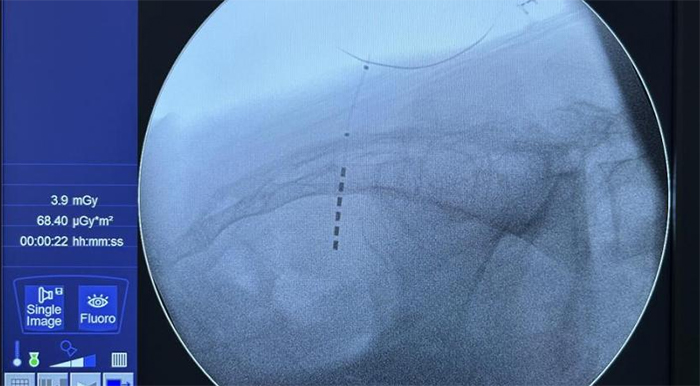

图为新型6触点电极成功植入患者体内

该患者为一例难治性膀胱过度活动症(OAB)的年轻女性,尿频、夜尿14年,曾口服多种药物治疗均效果不佳。廖利民教授同陈国庆教授等团队成员进行了详细的讨论,决定为患者植入具有更多电极组合的新型6触点电极并进行体外电刺激治疗,期望获得更好的疗效。手术由廖利民教授带领陈国庆教授为患者实施。经过精准的穿刺和测试,6个触点均反应敏感,起效电压均小于2v,顺利将电极成功放入S3神经孔。新型6触点电极的成功植入,标志着中康在骶神经调控技术领域取得了重要突破,也是国产骶神经调控装置自主研发道路上的重大进步。